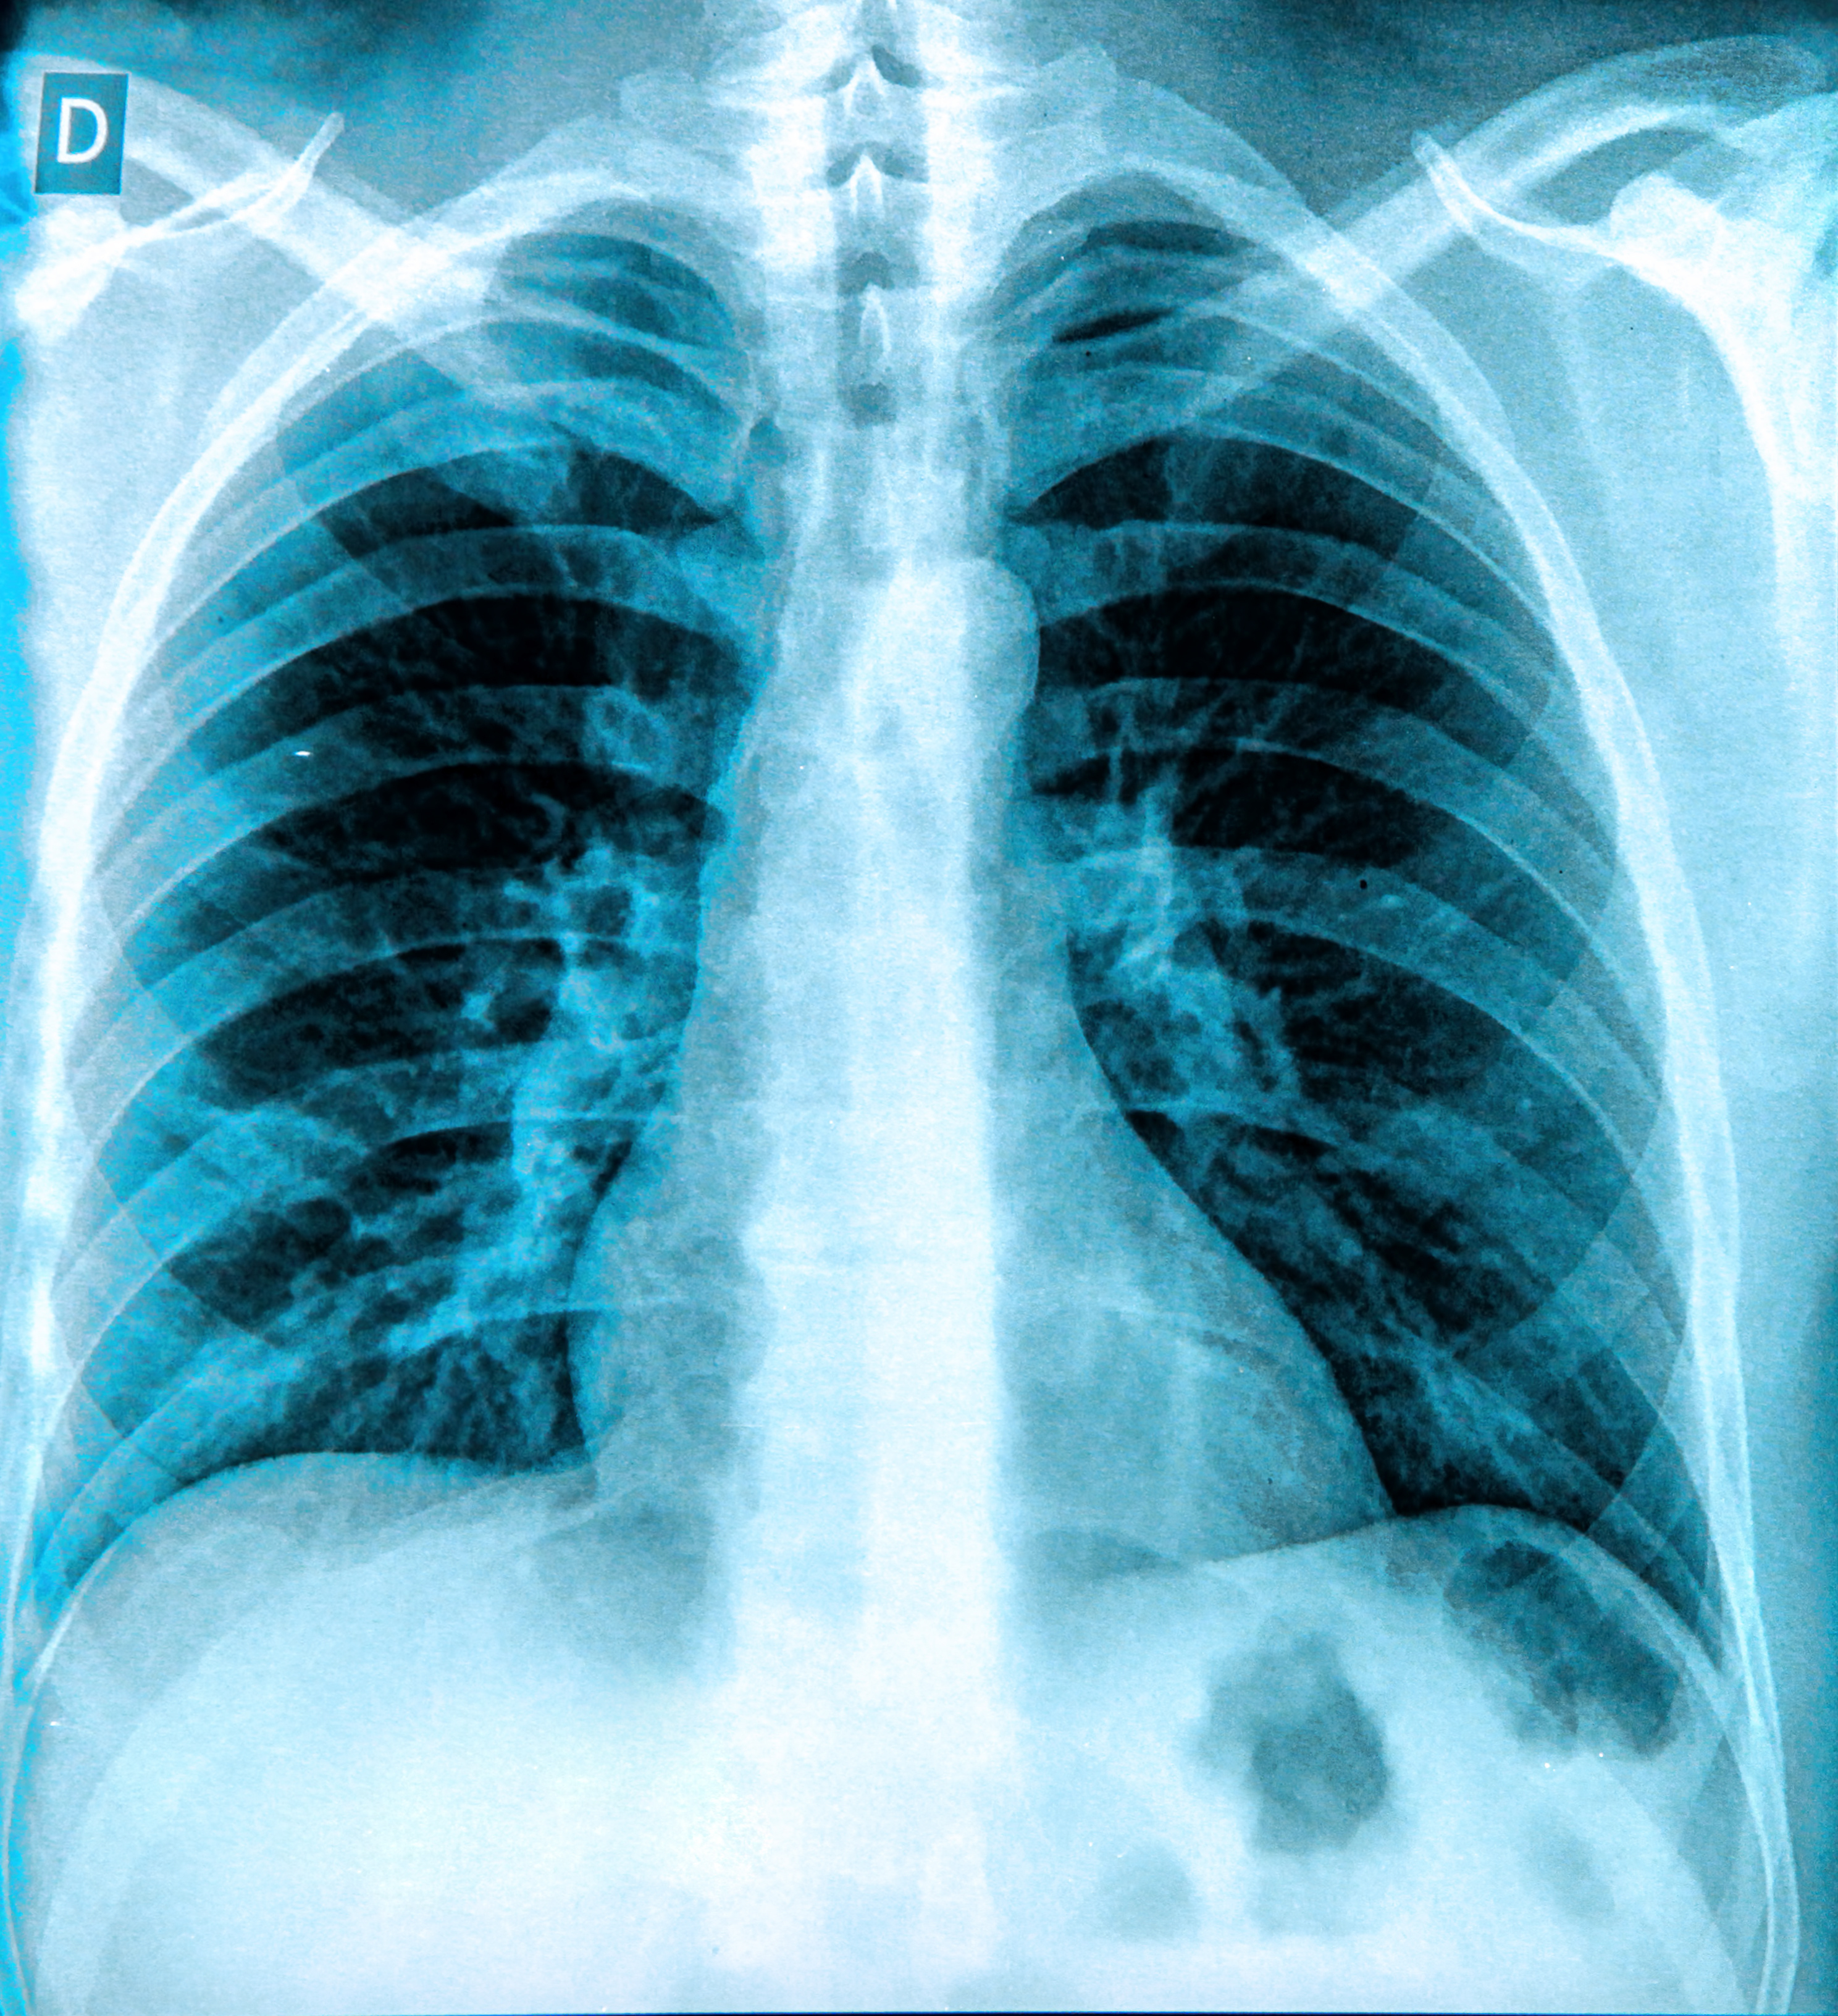

Digital chest tomosynthesis continues to attract plenty of interest, and because the technique enables lung cancer screening of high-risk individuals at a lower cost than CT, Italian researchers believe it could eventually become a "mammogram for the lungs." They presented their evidence in mid-April at the European Lung Cancer Conference in Geneva. Get the story here.